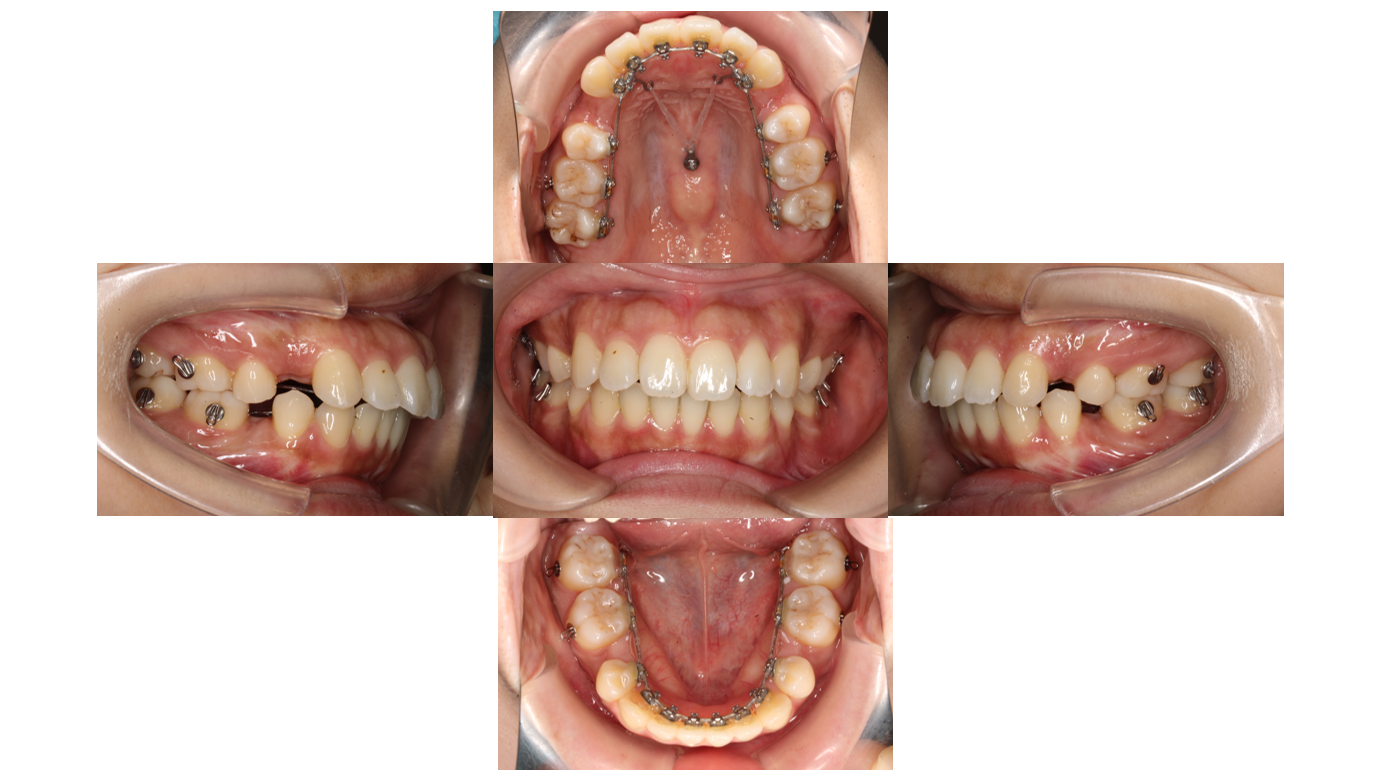

1年8か月経過

前回と同様に前歯を後ろに下げます

2年経過

全体的にゴムをかけて隙間が空いてこないようにします